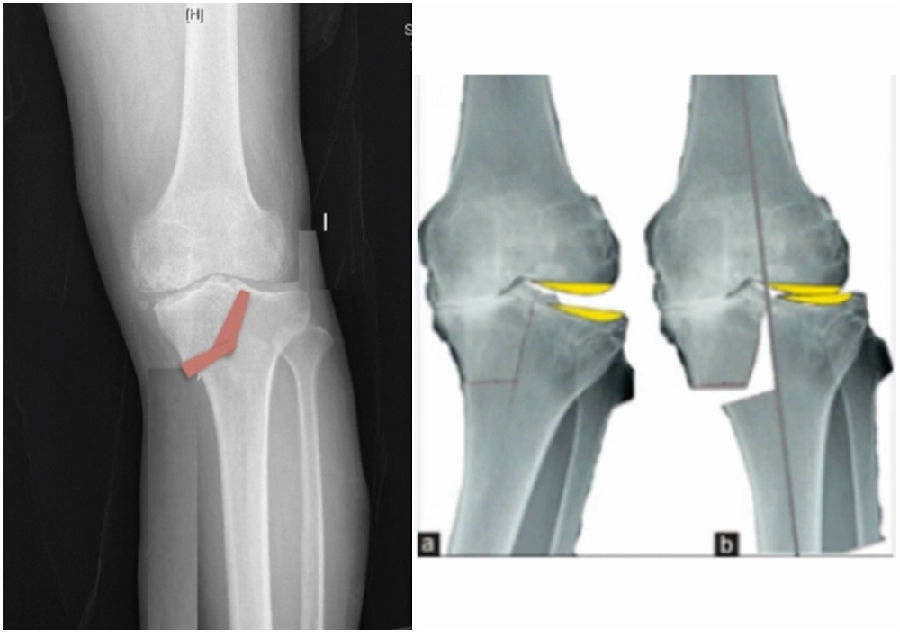

4OWHTO对髌骨高度影响?

1OWHTO可分为上行性或下行性两种截骨方式。

2)上行性OWHTO可降低髌骨高度的2%-11%;当髌骨高度下降10%,可引起髌股关节压力改变,引发膝前痛。

OWHTO上行截骨与下行截骨

3)下行性OWHTO对髌骨高度影响较小。

4)术前存在低位髌骨、髌股关节炎或内翻矫正度数较大时可考虑下行性OWHTO

有文献证实下行截骨对髌骨的高度确实没有明显影响。

OWHTO下行截骨对髌骨的影响